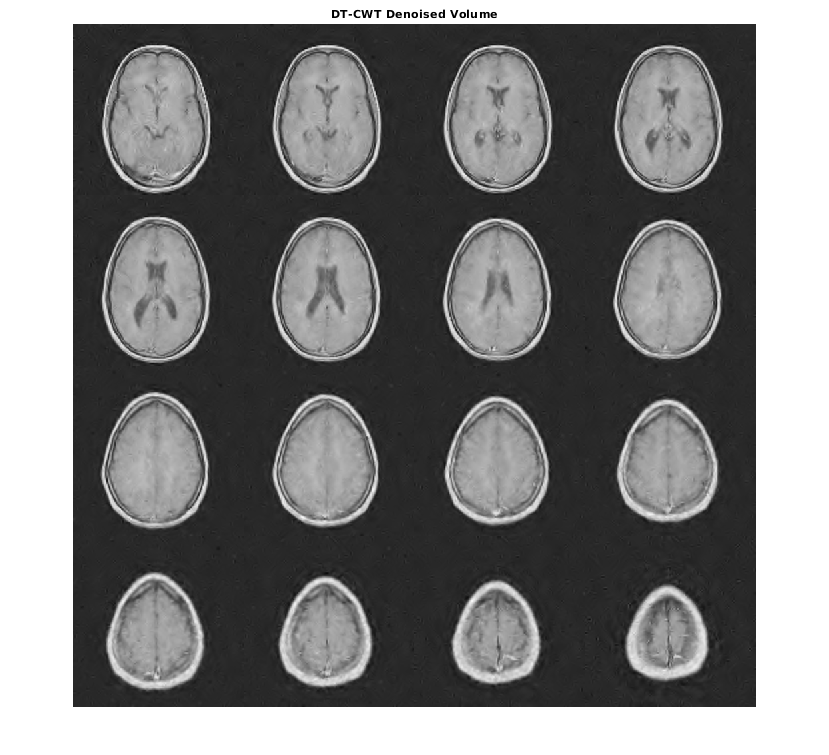

Чтобы продемонстрировать это, рассмотрите набор данных MRI, состоящий из 16 срезов. Гауссов шум со стандартным отклонением 10 был добавлен к исходному набору данных. Отобразите шумный набор данных.

load MRI3D; montage(reshape(noisyMRI,[128 128 1 16]),'DisplayRange',[]);

Обратите внимание на то, что исходный ОСШ до шумоподавления составляет приблизительно 11 дБ.

Denoise набор данных MRI вниз к уровню 4 с помощью и DT-CWT и DWT. Подобные длины фильтра вейвлета используются в обоих случаях. Постройте получившийся ОСШ как функцию порога. Отобразите результаты denoised и для DT-CWT и для DWT, полученного в лучшем ОСШ.

[imrecDTCWT,imrecDWT] = helperCompare3DDenoising(origMRI,noisyMRI); figure; montage(reshape(imrecDTCWT,[128 128 1 16]),'DisplayRange',[]); title('DT-CWT Denoised Volume'); figure; montage(reshape(imrecDWT,[128 128 1 16]),'DisplayRange',[]); title('DWT Denoised Volume');

Мы показали, что двойной древовидный DWT обладает желательными свойствами близкой инвариантности сдвига и направленной селективности, не достижимой с критически выбранным DWT. Мы продемонстрировали, как эти свойства могут привести к улучшенной производительности в анализе сигнала, представлении ребер в изображениях и объемах, и шумоподавлении объема и изображении.